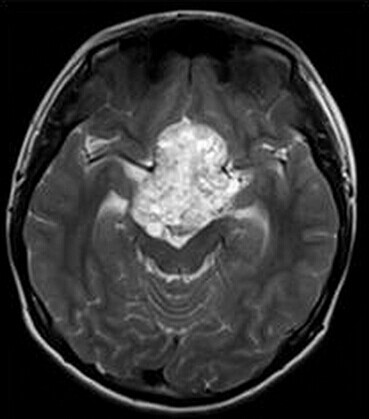

患者:男,15岁,双眼视力下降1年余,近来有嗜睡表现。

【正确答案】A 颅咽管瘤

(1)颅咽管瘤的两个发病高峰年龄分别是4-15岁和35-45岁,其中实性颅咽管瘤多见于成年人,本例为青少年患者,发病年龄无特异性;

(2)对诊断有提示意义的征象是明显强化,内散在微囊状不强化区。